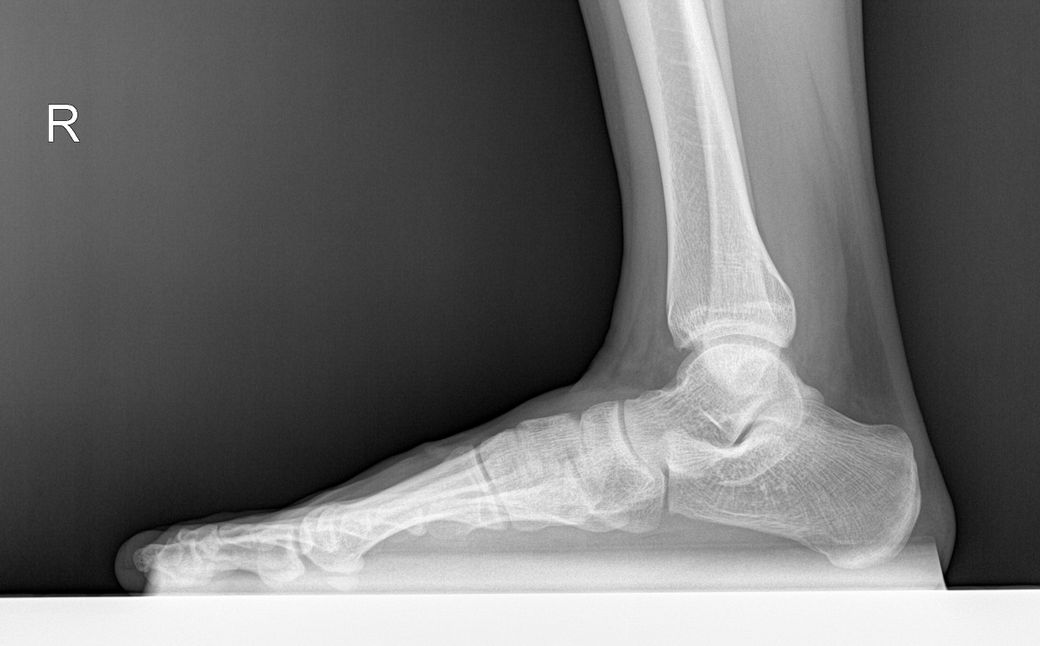

평발 측정을 위해 거골 - 제1중족골 각도가 궁금합니다.

• 2번 째 사진

우측보단 좌측발이 좀더 meary angle이 나올것으로 보이나 전체적으로 심하지 않은 편입니다.